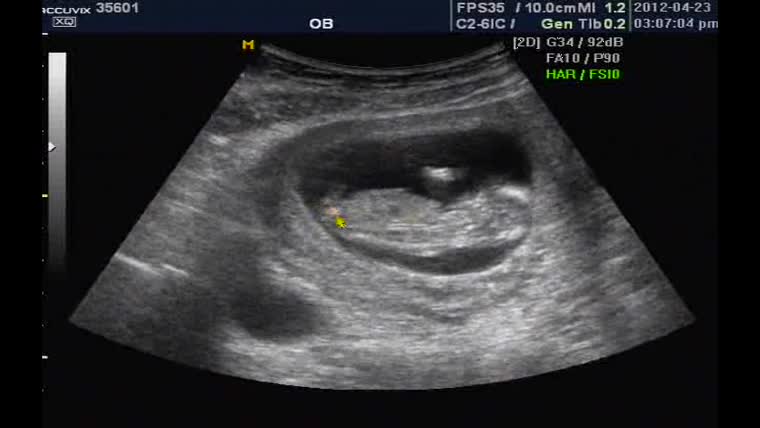

35601_baby.jpg (129.72 KB, 다운수: 674)

오현경 님이 2013-01-17 12:30에 등록 이름만 들어도 반가운 산모분! 그렇게 기다리던 덩이를 배에 품고 새벽에 오던날! 분만실에서 손 꼭 잡고, ...

이수진 님이 2013-01-17 18:46에 등록 덩이가 어느덧 백일이 다되어가고 있는 지금에서야 축하 글을 올립니다. ^^ 배가 좀 많이 불러 보이시던 ...

심상덕 님이 2013-01-18 14:35에 등록 출산을 축하합니다. 저희 병원 첫 출산일까 기대했는데 진통이 조금 늦게 오는 바람에 2호 출산 산모가 되 ...